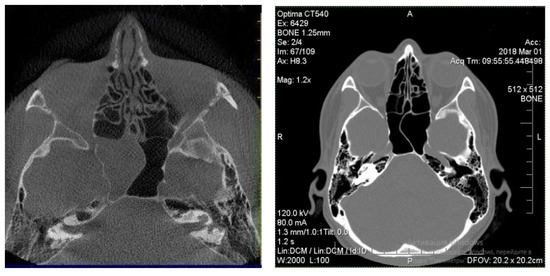

Patients with good outcomes after the treatment, which included residual edematous changes of the sinus mucosa on the CT scan, were designated as group 1 of the study (Figure 2) [18]. This group included 22 patients aged from 6 to 68 years old.

Figure 2. CT-scan of a patient, who showed good outcomes after conservative treatment and was added to group 1.